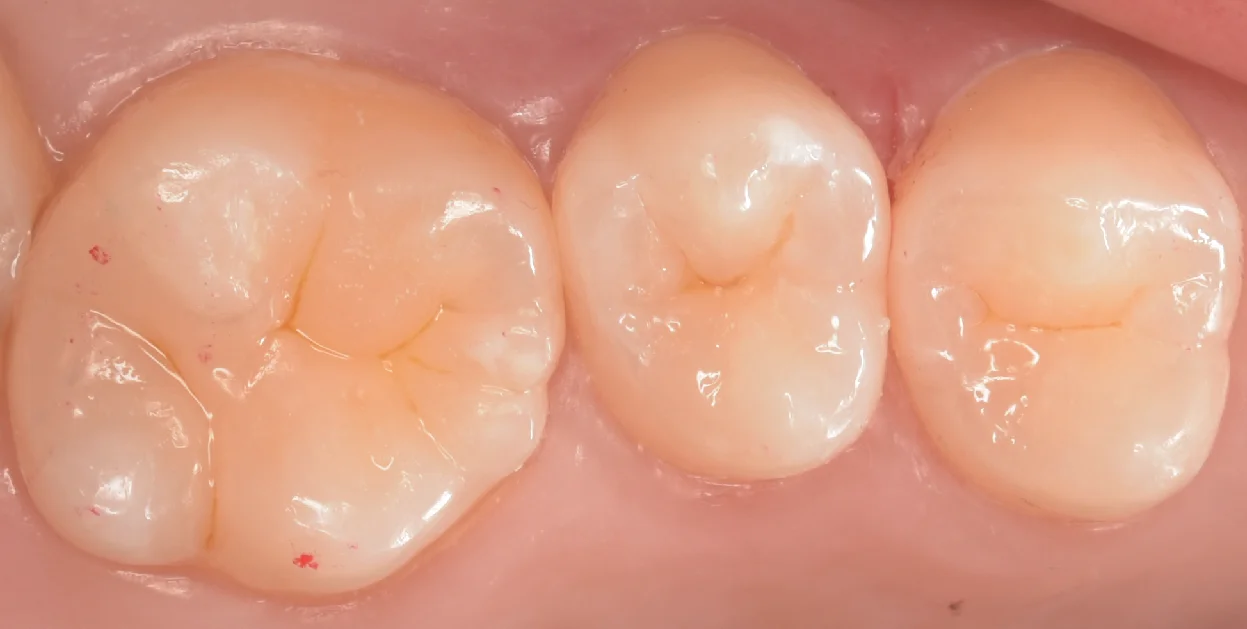

そして治療完了後の写真がこちらになります。

違和感なく綺麗に詰め終われたかと思います。